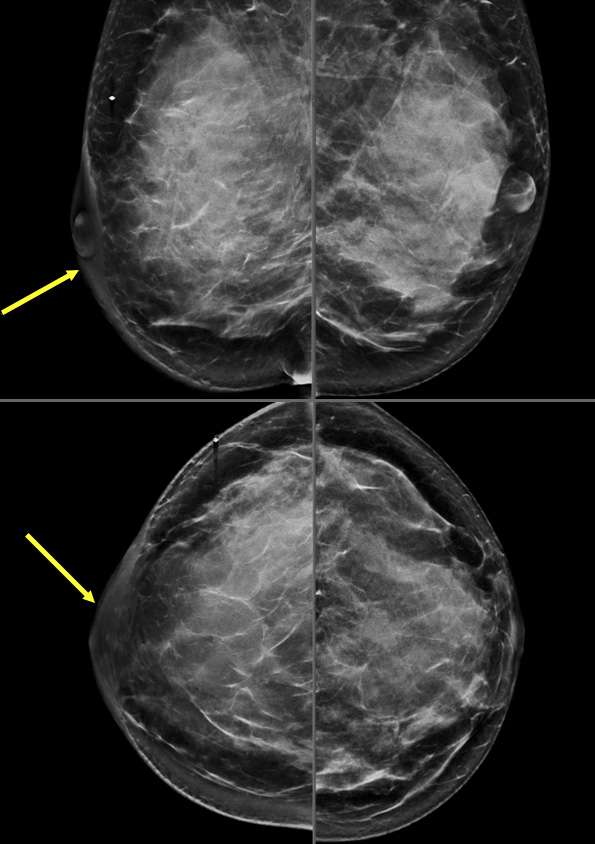

Case: Skin and Nipple Changes

Figure 1: Skin Retraction on Mammogram. Patient presented for a palpable lump in the left breast. Mammographic MLO and CC projections demonstrate an irregular spiculated mass with associated architectural distortion (circle), and overlying skin retraction (arrows) in the upper outer quadrant of the left breast. Right side is included for comparison.